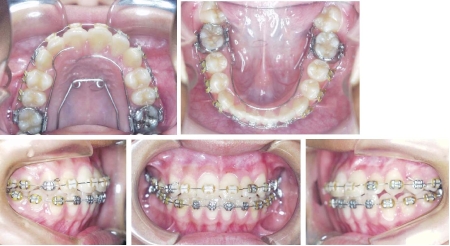

| 治療中